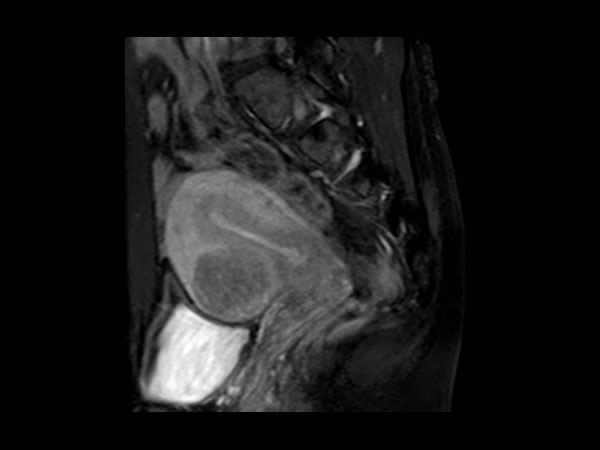

Female Pelvis

Toyonaka Hospital, Japan